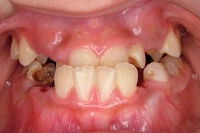

CASE5

小学1年の頃から前歯の噛み合せが逆でした。

同級生が通っていたので来ました。

(11歳/男性)↓

概要・担当医コメント:反対咬合・前歯部咀嚼障害↑

/マルチブラケット装置/非抜歯/動的治療期間24ヶ月(25回)/費用概算:60万円

治療前は虫歯のコントロールが難しい状態でしたが,矯正治療を開始してからは歯磨きを丁寧にしてくれるようになり,甘味摂取習慣の改善も行って頂いた効果があり,その後の虫歯の発生は無く現在に至っています.